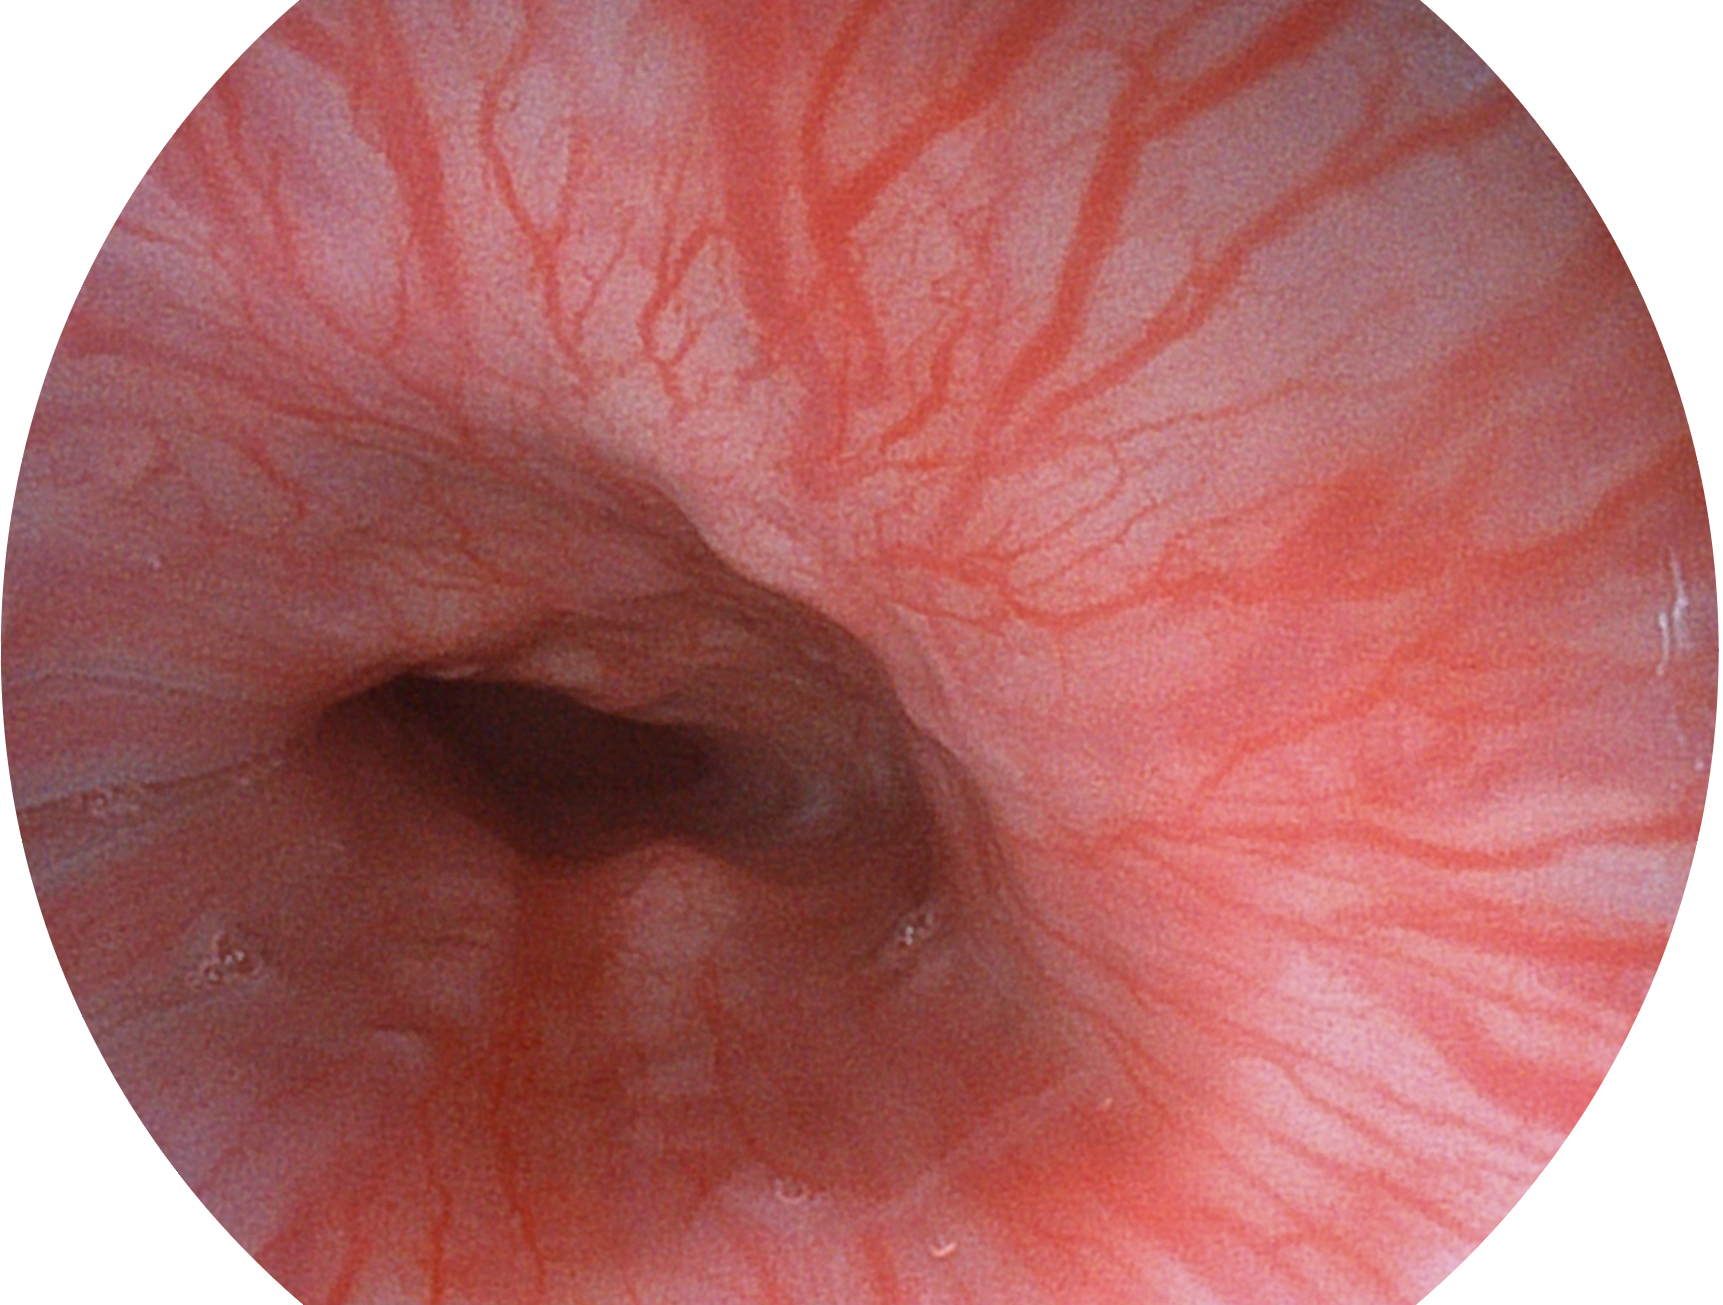

• 白光图像 SFI图像